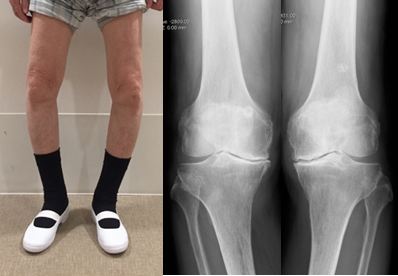

両側O脚変形、両側同時TKA

脛骨の近位部を骨切りし、O脚に変形した下肢を軽度X脚に矯正し、荷重による負担を膝外側に移動することによって、膝内側の痛みを緩和する方法です。変形の程度によって開大式と閉鎖式骨切り術を使い分けております。